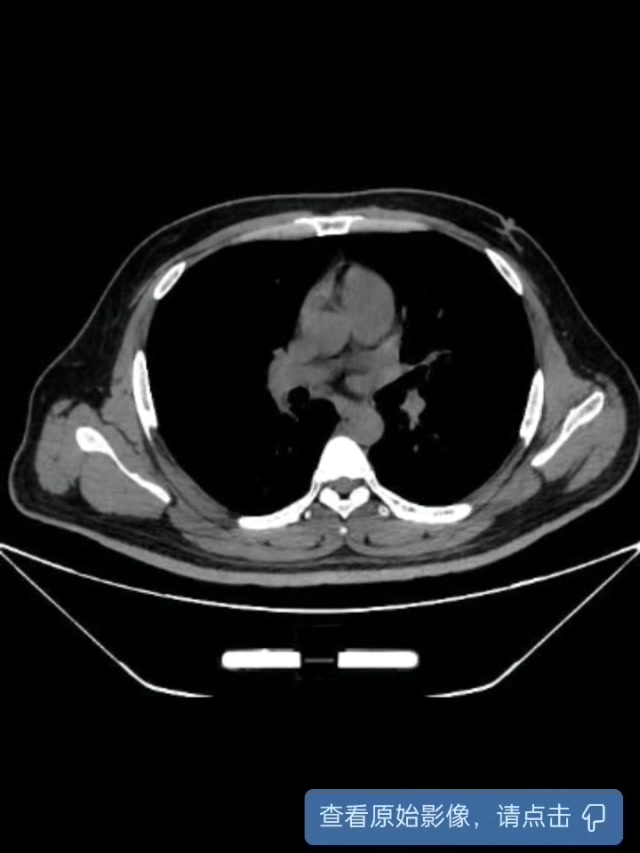

我院腹部CT: